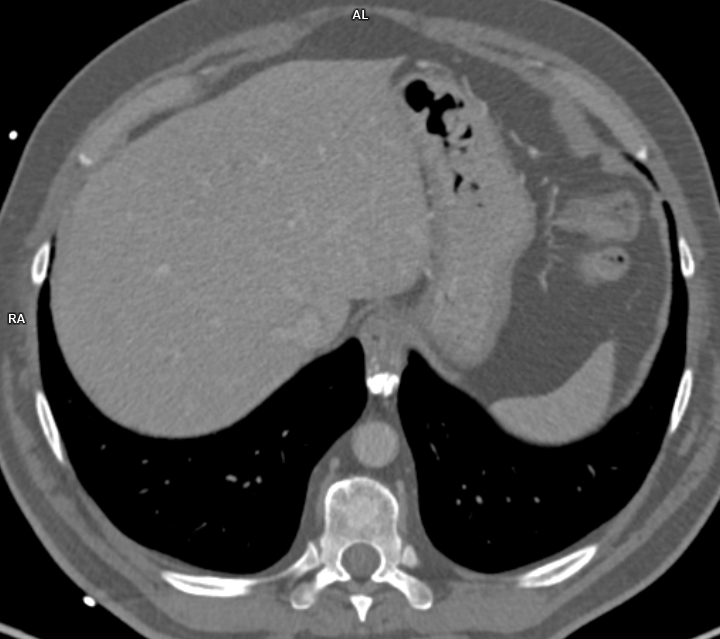

Figura 4: CT axial postcontrast în timp venos

Leiomiomul esofagian este un neoplasm benign al musculaturii netede a esofagului, fiind cea mai frecventă tumoare benignă a esofagului. Clinica depinde de dimensiunea tumorii, fiind asimptomatice dacă au dimensiuni mai mici de 5 cm iar tumorile mari pot provoca disfagie, regurgitare, obstrucție esofagiană, dureri în piept, tuse sau sângerare. Examinarea CT pune în evidenţă o formațiune solitară intramurală ovoidală având contur net iar prezența calcificărilor este aproape patognomonică – leziunile se pot dezvolta atât spre lumenul esofagian cat si spre seroasă, fără semne de invazie a țesuturilor de vecinătate.

Leziunile expansive esofagiene benigne cu dimensiuni sub 5 cm sunt descoperiri întâmplătoare la examinările CT toracice pentru alte patologii cu excepția celor ce afectează joncțiunea eso-gastrică. Pentru leiomiomul esofagian, patognomonice sunt calcificările cu aspect muriform.